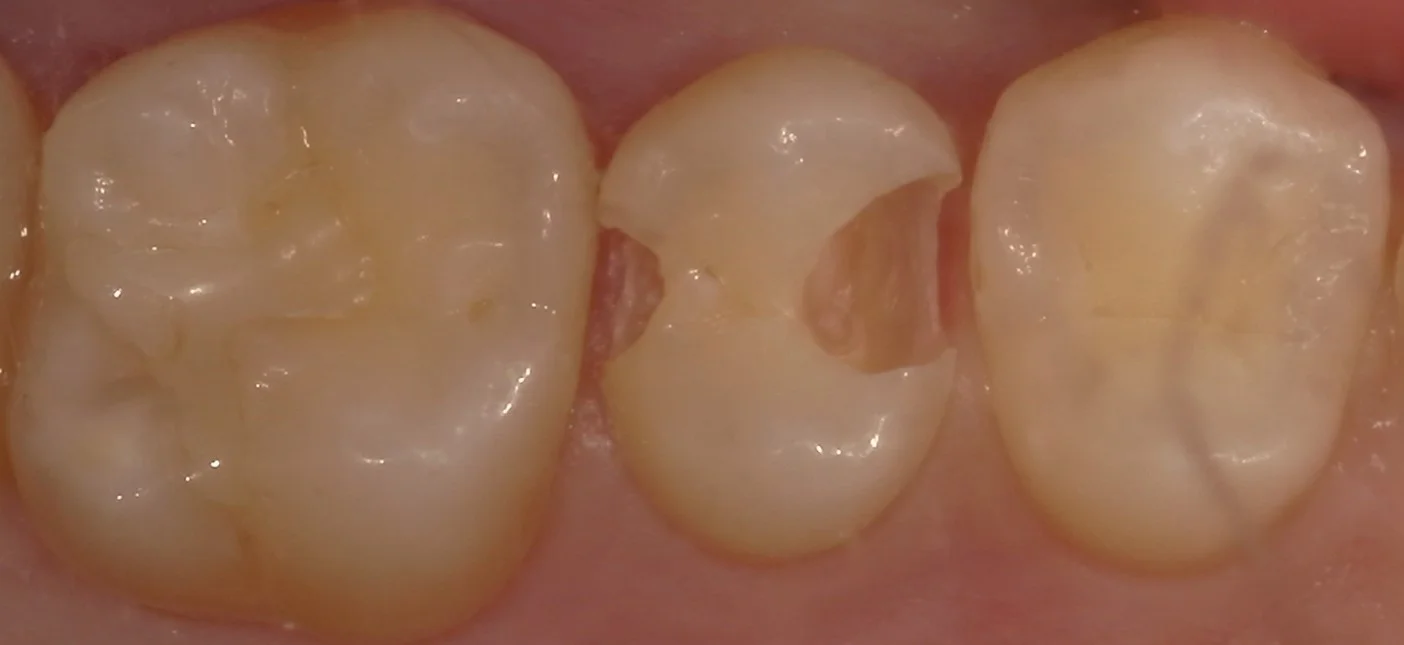

なので、虫歯を取りきってみると・・・

こんな感じで、非常に大きく虫歯になっていました。

実は外側の歯はもうほとんど残っておらず、最表層のエナメル質という構造のみが残存している状況になっていました。

今回はインレーにされていたりしたわけではなく、全く他の先生に触られていない状態だったため、非常に大きく歯を温存することが出来ました。